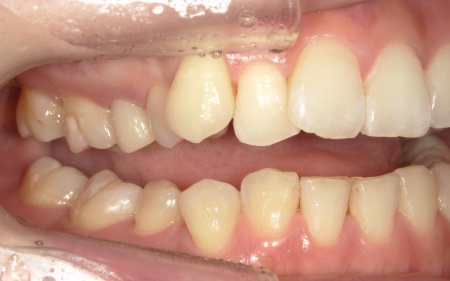

20代女性 前歯の歯並びをマウスピース矯正装置インビザラインGoで改善した症例

拝見したところ、叢生(そうせい)が上下前歯に確認できました。

今回のケースでは上前歯にやや目立つ重なりがあり、下前歯は軽度の叢生が見られました。

一方で奥歯の噛み合わせについては、大きなズレや機能的な問題はありませんでした。